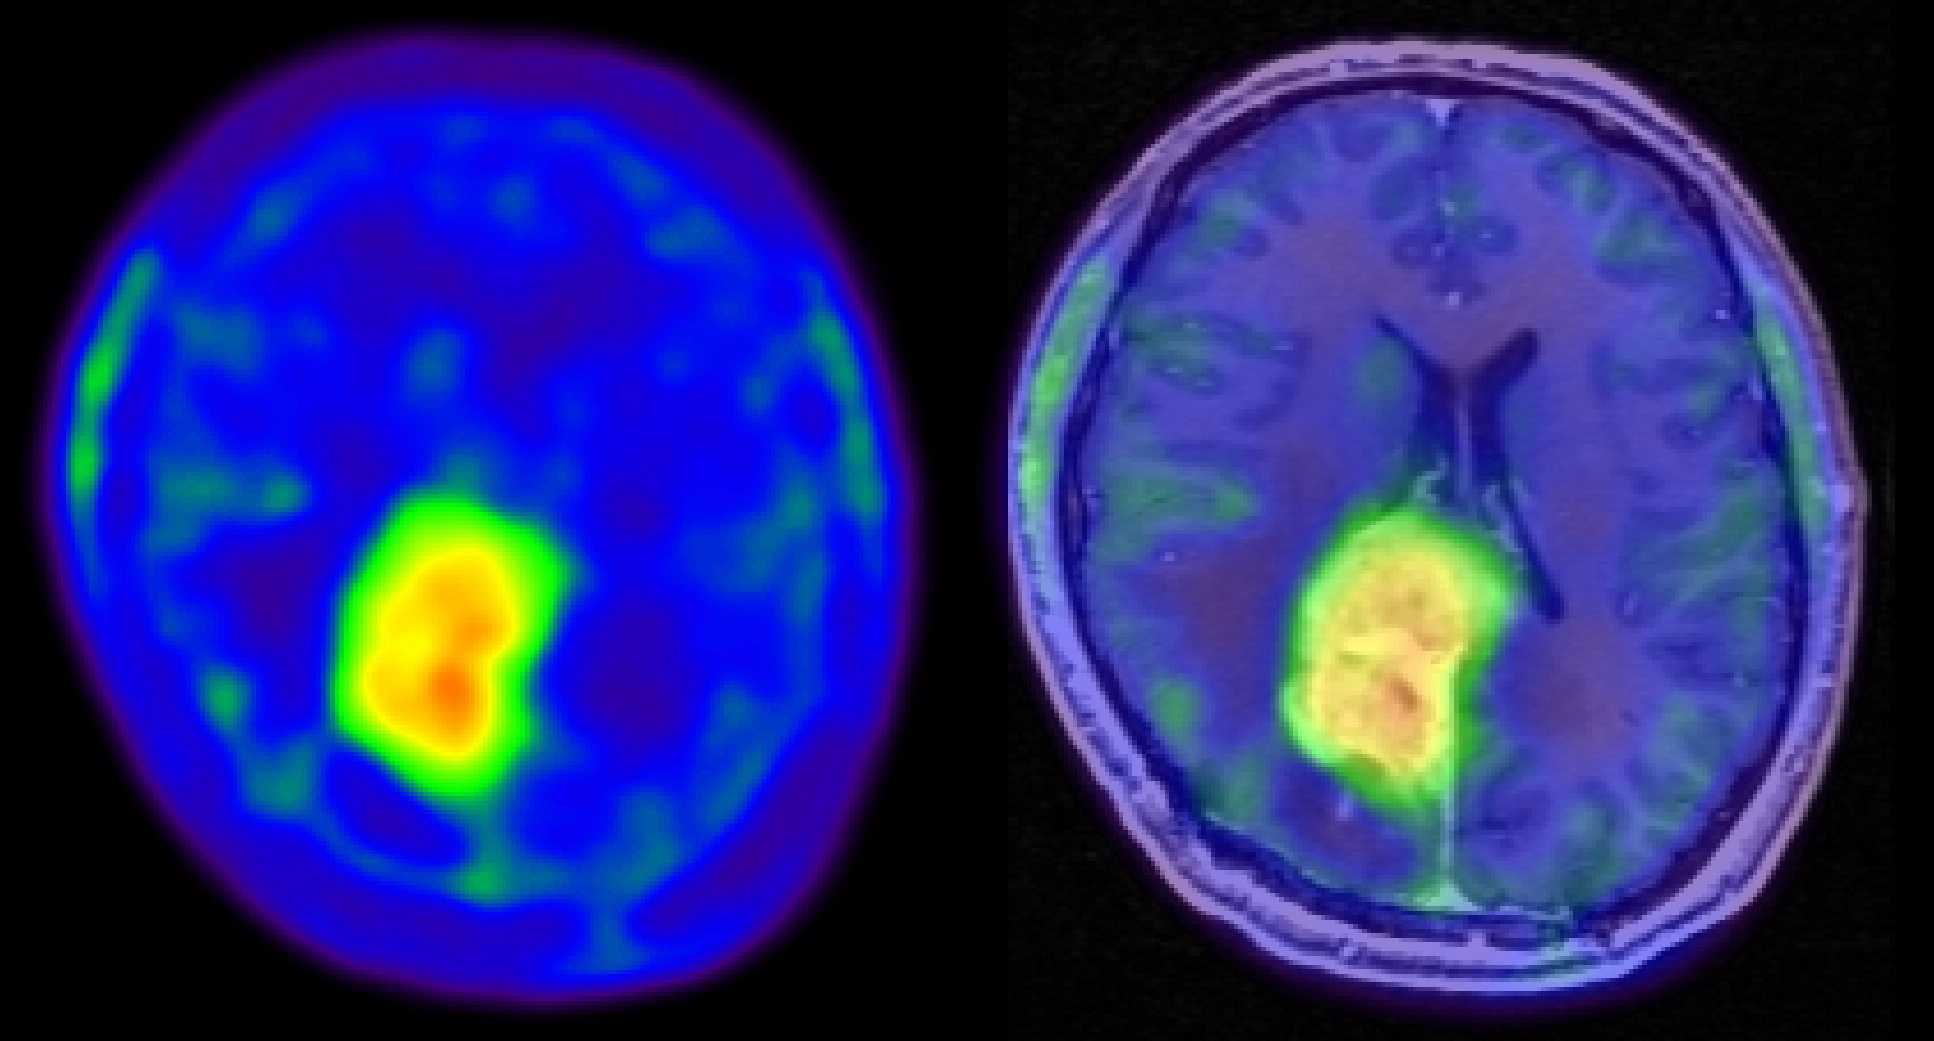

In Deutschland erkranken jährlich circa 7.000 Menschen an Gehirntumoren. Die häufigste und zugleich bösartigste Tumorart ist das Glioblastom, ein sehr schnell wachsender Tumor, der im Hirngewebe selbst entsteht. Patienten mit dieser Diagnose erwartet eine anstrengende und langwierige Behandlung mit Operationen, Bestrahlung und Chemotherapie – bisher ohne Chance auf vollständige Heilung. Das Zentrum für Hirntumoren des Universitätsklinikums Regensburg (UKR) erstellt jetzt in interdisziplinärer Zusammenarbeit eine Patienten- und Gewebedatenbank für Hirntumoren. Ziel ist es, die Entstehung von Gehirntumoren zu untersuchen und noch wirksamere Behandlungsmethoden zu entwickeln.

Um Lebenszeit und Lebensqualität der Patienten so lange wie möglich zu erhalten, widmen sich Ärzte und Forscher am Universitätsklinikum Regensburg seit Jahren der Verbesserung von Diagnostik und Therapie bei Gehirntumoren. Das UKR unterhält mit dem 2009 gegründeten Zentrum für Hirntumoren (ZHT) eines der größten Forschungs- und Behandlungszentren in Deutschland. Das Zentrum wird seit drei Jahren durch die von der Wilhelm Sander-Stiftung geförderte Therapieeinheit „NeuroOnkologie“ gestärkt. Unter deren Federführung startet nun ein neues Projekt: In interdisziplinärer Zusammenarbeit zwischen UKR, medbo (medizinische Einrichtungen des Bezirks Oberpfalz) Bezirksklinikum Regensburg und Tumorzentrum Regensburg wird eine Patienten- und Gewebedatenbank für Gehirntumoren eingerichtet. Die systematisch erfassten und ausgewerteten Diagnose- und Behandlungsdaten von Patienten sollen wichtige Erkenntnisse bringen, um die Behandlungsmethoden weiterzuentwickeln.